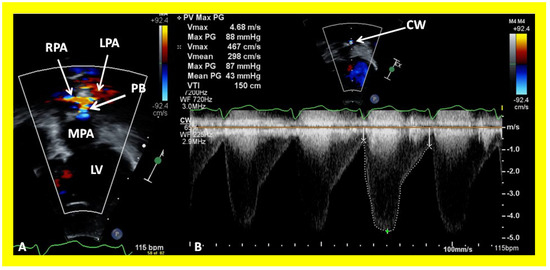

In patients who had banding of the PA, echo-Doppler studies should be scrutinized to demonstrate the banded PA diameter (Figure 22A,B and Figure 23A) and peak Doppler flow velocity across the banded PA (Figure 22C and Figure 23B); high Doppler velocity across the band (Figure 22C and Figure 23B) would suggest effective palliation. Low gradients and ineffective control of CHF may require tightening of the band; echo-Doppler evaluation is useful in making such an assessment.

Figure 22. Selected echocardiographic video frames demonstrating pulmonary artery band (PAB) with narrow diameter of 2.9 mm by 2D (A) and by color flow (B) and a high gradient (81 mmHg) by continuous wave Doppler (C) are shown.

Figure 23. Selected echocardiographic video frames demonstrating pulmonary artery band (PAB) with narrow diameter by color flow (A) and a high gradient (88 mmHg) by continuous wave Doppler (B) are shown.